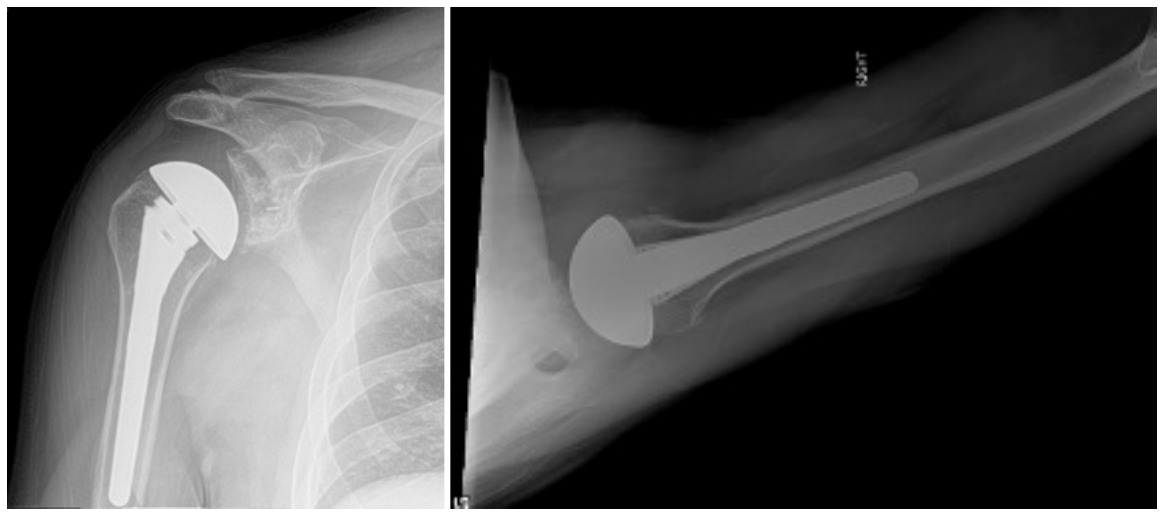

Case one is a 58-year-old male who is an avid golfer with long standing right shoulder pain. Surgical history includes previous Bristow procedure 30 years prior. Current Subjective Shoulder Value (SSV) is 30% and pain is 8/10 at baseline. Active range of motion was 110° of forward flexion, -10° of external rotation and interna rotation to the lateral buttock. Radiographs (Figure 1) and computed topography (CT) scan (Figure 2) show retained implants with loss of joint space, glenoid retroversion, and significant posterior humeral head subluxation. The patient had failed conservative management and was indicated for arthroplasty. Due to significant posterior bone loss and retroversion, an augmented anatomic component was selected for this patient. Radiographs at one year show a well seated glenoid component with restoration of the joint line and a centered humeral head (Figure 3). At five years, SSV had improved to 95% with excellent clinical motion (Figure 4).

Case two is an 86-year-old female with long standing left shoulder pain and loss of function. Preoperative exam shows 70° of active forward flexion, neutral external rotation, and internal rotation to the lateral thigh. Radiographs (Figure 5) and CT scan (Figure 6) show significant posterior bone loss and retroversion with medialization of the joint line. Options include asymmetric reaming, an augmented component, or bone grafting. An augmented reverse baseplate was selected for this elderly female. Radiographs at six months show a well fixated baseplate with improvement of the pre-operative retroversion (Figure 7).